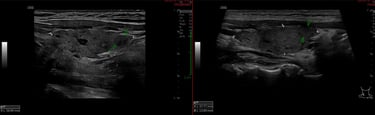

Regeneración del lóbulo derecho del tiroides con desaparicion de quistes coloides y casi normalización de la estructura de un nódulo sólido